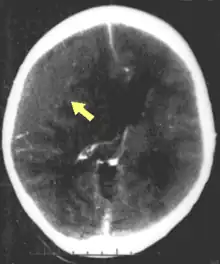

Movement disorders that may develop after TBI include tremor, ataxia (uncoordinated muscle movements), spasticity (muscle contractions are overactive), myoclonus (shock-like contractions of muscles), and loss of movement range and control (in particular with a loss of movement repertoire).[31][33] The risk of post-traumatic seizures increases with severity of trauma (image at right) and is particularly elevated with certain types of brain trauma such as cerebral contusions or hematomas.[34] People with early seizures, those occurring within a week of injury, have an increased risk of post-traumatic epilepsy (recurrent seizures occurring more than a week after the initial trauma).[35] People may lose or experience altered vision, hearing, or smell.[24]

Hematomas, also focal lesions, are collections of blood in or around the brain that can result from hemorrhage.[24] Intracerebral hemorrhage, with bleeding in the brain tissue itself, is an intra-axial lesion. Extra-axial lesions include epidural hematoma, subdural hematoma, subarachnoid hemorrhage, and intraventricular hemorrhage.[105] Epidural hematoma involves bleeding into the area between the skull and the dura mater, the outermost of the three membranes surrounding the brain.[24] In subdural hematoma, bleeding occurs between the dura and the arachnoid mater.[32] Subarachnoid hemorrhage involves bleeding into the space between the arachnoid membrane and the pia mater.[32] Intraventricular hemorrhage occurs when there is bleeding in the ventricles.[105]